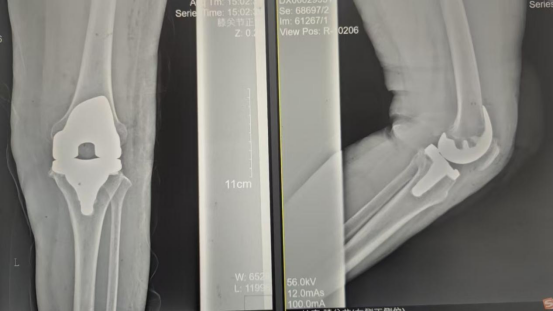

術(shù)后影像資料

手術(shù)當(dāng)天張女士懷著忐忑的心情進(jìn)入手術(shù)室,然而伴隨著麻醉醫(yī)師的和藹交談和手術(shù)護(hù)士的溫馨叮嚀,在不知不覺(jué)中慢慢睡著,手術(shù)非常順利。術(shù)后經(jīng)醫(yī)護(hù)人員的精心治療與護(hù)理,張女士康復(fù)出院,最終解決了10余年的病痛。

因張女士患有高血壓病2級(jí)(高危)、心律失常(竇緩)且伴有肺部感染等并發(fā)癥。穆志亮主任和葉龍安主治醫(yī)師根據(jù)張女士的病情制定詳細(xì)手術(shù)方案,建議在全麻下行“左人工全膝關(guān)節(jié)置換術(shù)”。